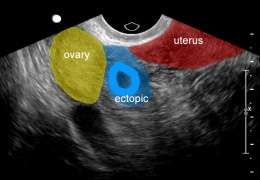

Ectopic pregnancy

- Implantation of blastocyst outside of endometrium

- Occur in fallopian tubes, cervix, ovaries, peritoneal cavity, or scar of prior uterine surgery

- Most definitive sonographic sign is gestational sac with yolk sac, embryo, or fetal heart beat outside of the endometrium

- Tubal pregnancy

- "Tubal ring" sign: echogenic thick-walled anechoic sac visualized between uterus and ovary (separate from ovary when pressure applied to fallopian tube with probe)

Ectopic pregnancy

Ectopic pregnancy Free fluid in cul-de-sac with no gestational sac visualized in uterus

Free fluid in cul-de-sac with no gestational sac visualized in uterus Ectopic pregnancy between ovary and uterus, suggestive of tubal ectopic

Ectopic pregnancy between ovary and uterus, suggestive of tubal ectopic Interstitial pregnancy